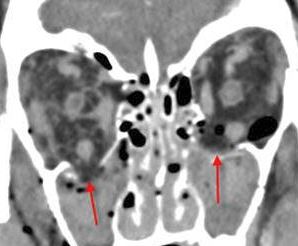

Orbits and Orbital Zygomatic Complex

The preseptal soft tissues including the lacrimal gland and sac are abnormal.

There is evidence of a subperiosteal hematoma along the medial or lateral wall, roof or floor of the orbit.

The circumferential extraconal and the intraconal orbital fat are infiltrated.

There is evidence of bony injury along the walls and/or floor of the orbit.

The supraorbital and infraorbital rims and orbital process of the zygoma and/or frontozygomatic suture are fractured.